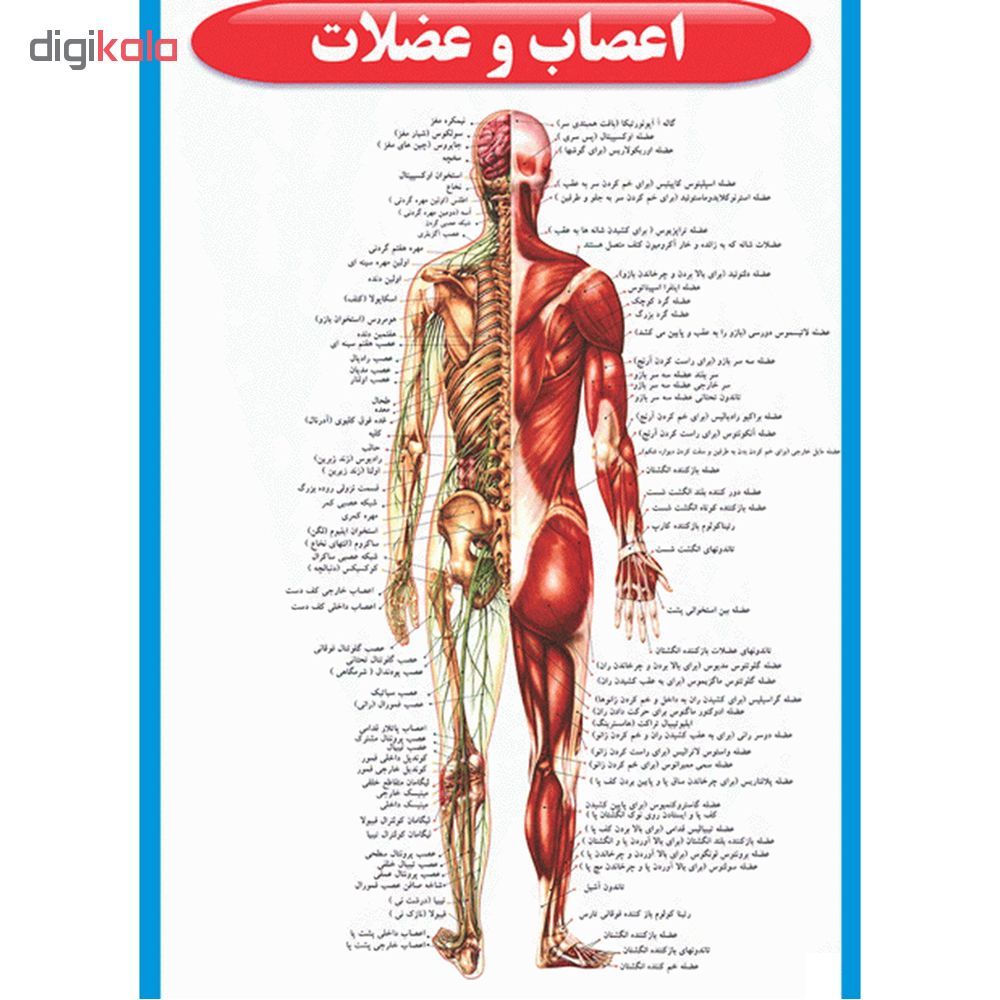

اسکلت جمجمه و گردن انسان ستون فقرات آناتومی اسکلت جمجمه و گردن انسان ستون فقرات آناتومی تصویر با کیفیت را از لینک زیر می توانید دانلود کنید. ۱ مطلب با کلمه ی کلیدی عکس اسکلت بدن انسان با کیفیت ثبت شده است گالری نسیم جدید ترین و با کیفیت ترین عکس های مناسبتی. عکس با کیفیت آناتومی اسکلت بدن انسان و درد و دیسک در قسمت مهره های ستون فقرات کمر ویژه استفاده در امور تبلیغاتی و تجاری طراحی کاتالوگ بروشور و تراکت با موضوع بیمارستان ها و کلینیک ها و درمانگاه ها و مطب ها پزشکان و.